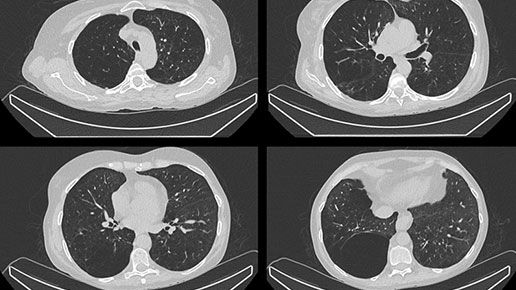

Clarify DL¹

Refocus with Clarify DL and move on from reading around the noise

Image quality has always required a trade-off between removing noise and maintaining contrast. GE HealthCare has a solution that mitigates that trade-off. Clarify DL is Aurora's AI-enabled bone SPECT image reconstruction designed to reduce noise, while retaining signal contrast. Doing so improves contrast-to-noise ratio (CNR) and contrast recovery coefficients (CRC)⁴, which are important factors in lesion detectability. With or without CT, Clarify DL is designed to achieve a new level of image quality performance without having to increase injected dose or scan time. Improved image quality performance may help increase diagnostic confidence.⁵ Clarify DL’s image resolution has been rated as better in 98% of exams.⁶

1. Clarify DL is available on Xeleris V

4. Clarify DL improves contrast recovery coefficient (CRC) up to 82% and contrast to noise ratio (CNR) up to 58% as compared to use of GE bone SPECT factory reconstruction presets for dual head cameras.* CRC and CNR are important factors in lesion detectability. *CRC and CNR demonstrated using digital phantom with inserted lesions of known size, location, and contrast, for AC and NC images.

5. Clarify DL improves dual head cameras’ image quality performance measured by Structures Similarity (SSIM) – up to 8% improvement, Mean Squared Error (MSE) up to 76% improvement, and Peak Signal-to-Noise Ratio (PSNR) - up to 18% improvement, as compared to GE bone SPECT factory reconstruction presets*. Improved image quality performance may help increase diagnostic confidence. *Demonstrated using digital phantom simulations with inserted lesions of known size, location, and contrast, for AC and NC images.

6. In 127 exams rated by total of 9 physicians, in 98% of the exams, Clarify DL’s image resolution was rated as better than the existing factory reconstruction preset images.* *As demonstrated in clinical evaluation, where each exam was reconstructed with both Clarify DL and the existing factory reconstruction preset and evaluated by 3 of the physicians.